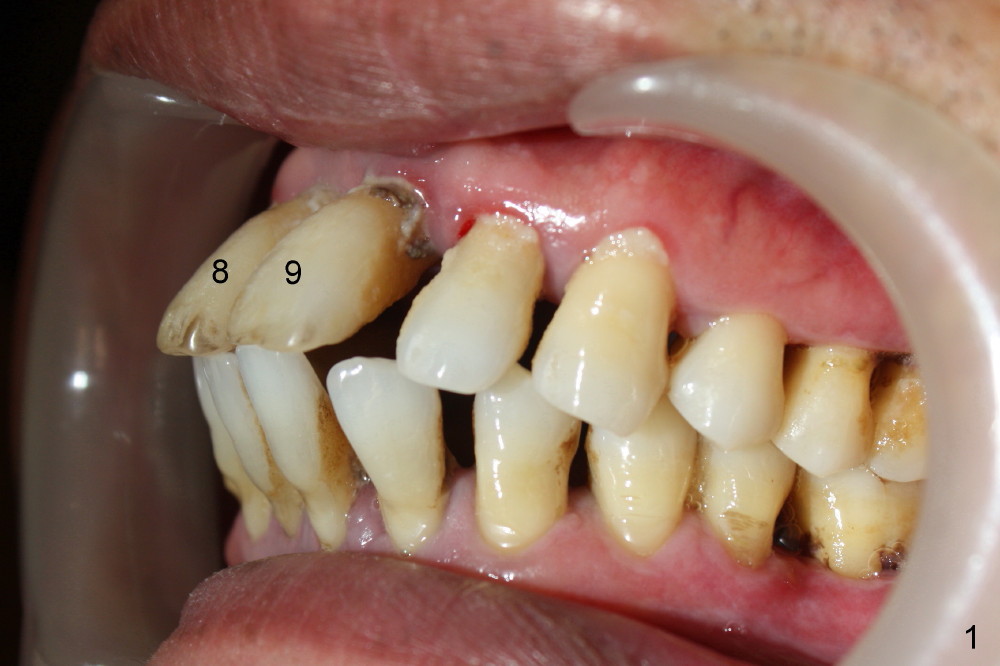

A 49-year-old man has severe chronic periodontitis. The upper central incisors are protrusive and mobile (Fig.1,2: #8,9), but the basal bone is wide and tall (BB in Fig.2). Immediate implants are going to be placed. To avoid malpositioning of the implant, initial osteotomy begins close to the palatal plate (Fig.3: P), while the axis of the osteotomy is parallel to and close to the buccal plate (>). The implant (Fig.4 pink), abutment (red) and the crown (white) will be in a favorable trajectory. To reduce protrusion, the incisal edge of the lower central will be trimmed (compare Fig.3 * and Fig.4 black area).